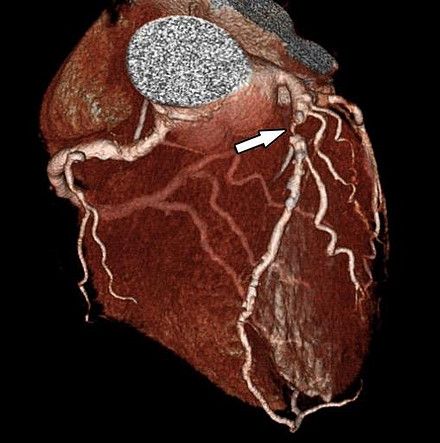

New research suggests an emerging machine learning model that combines findings from advanced imaging with clinical data may improve risk stratification in people with coronary artery disease.

What lesion is indicated by the arrows?